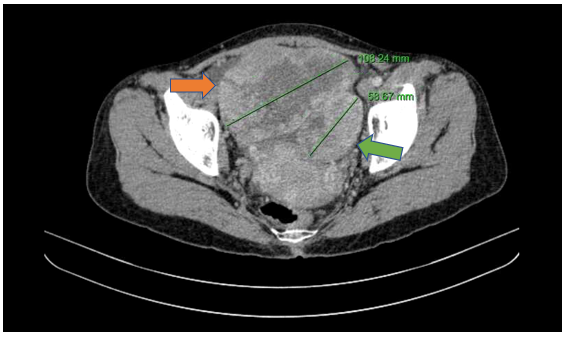

Hình 5

. Hình ảnh khối buồng trứng phải kích thước ~108mm (mũi tên màu cam), khối buồng trứng trái kích thước ~58mm (mũi tên màu xanh lục) trên phim chụp cắt lớp vi tính.